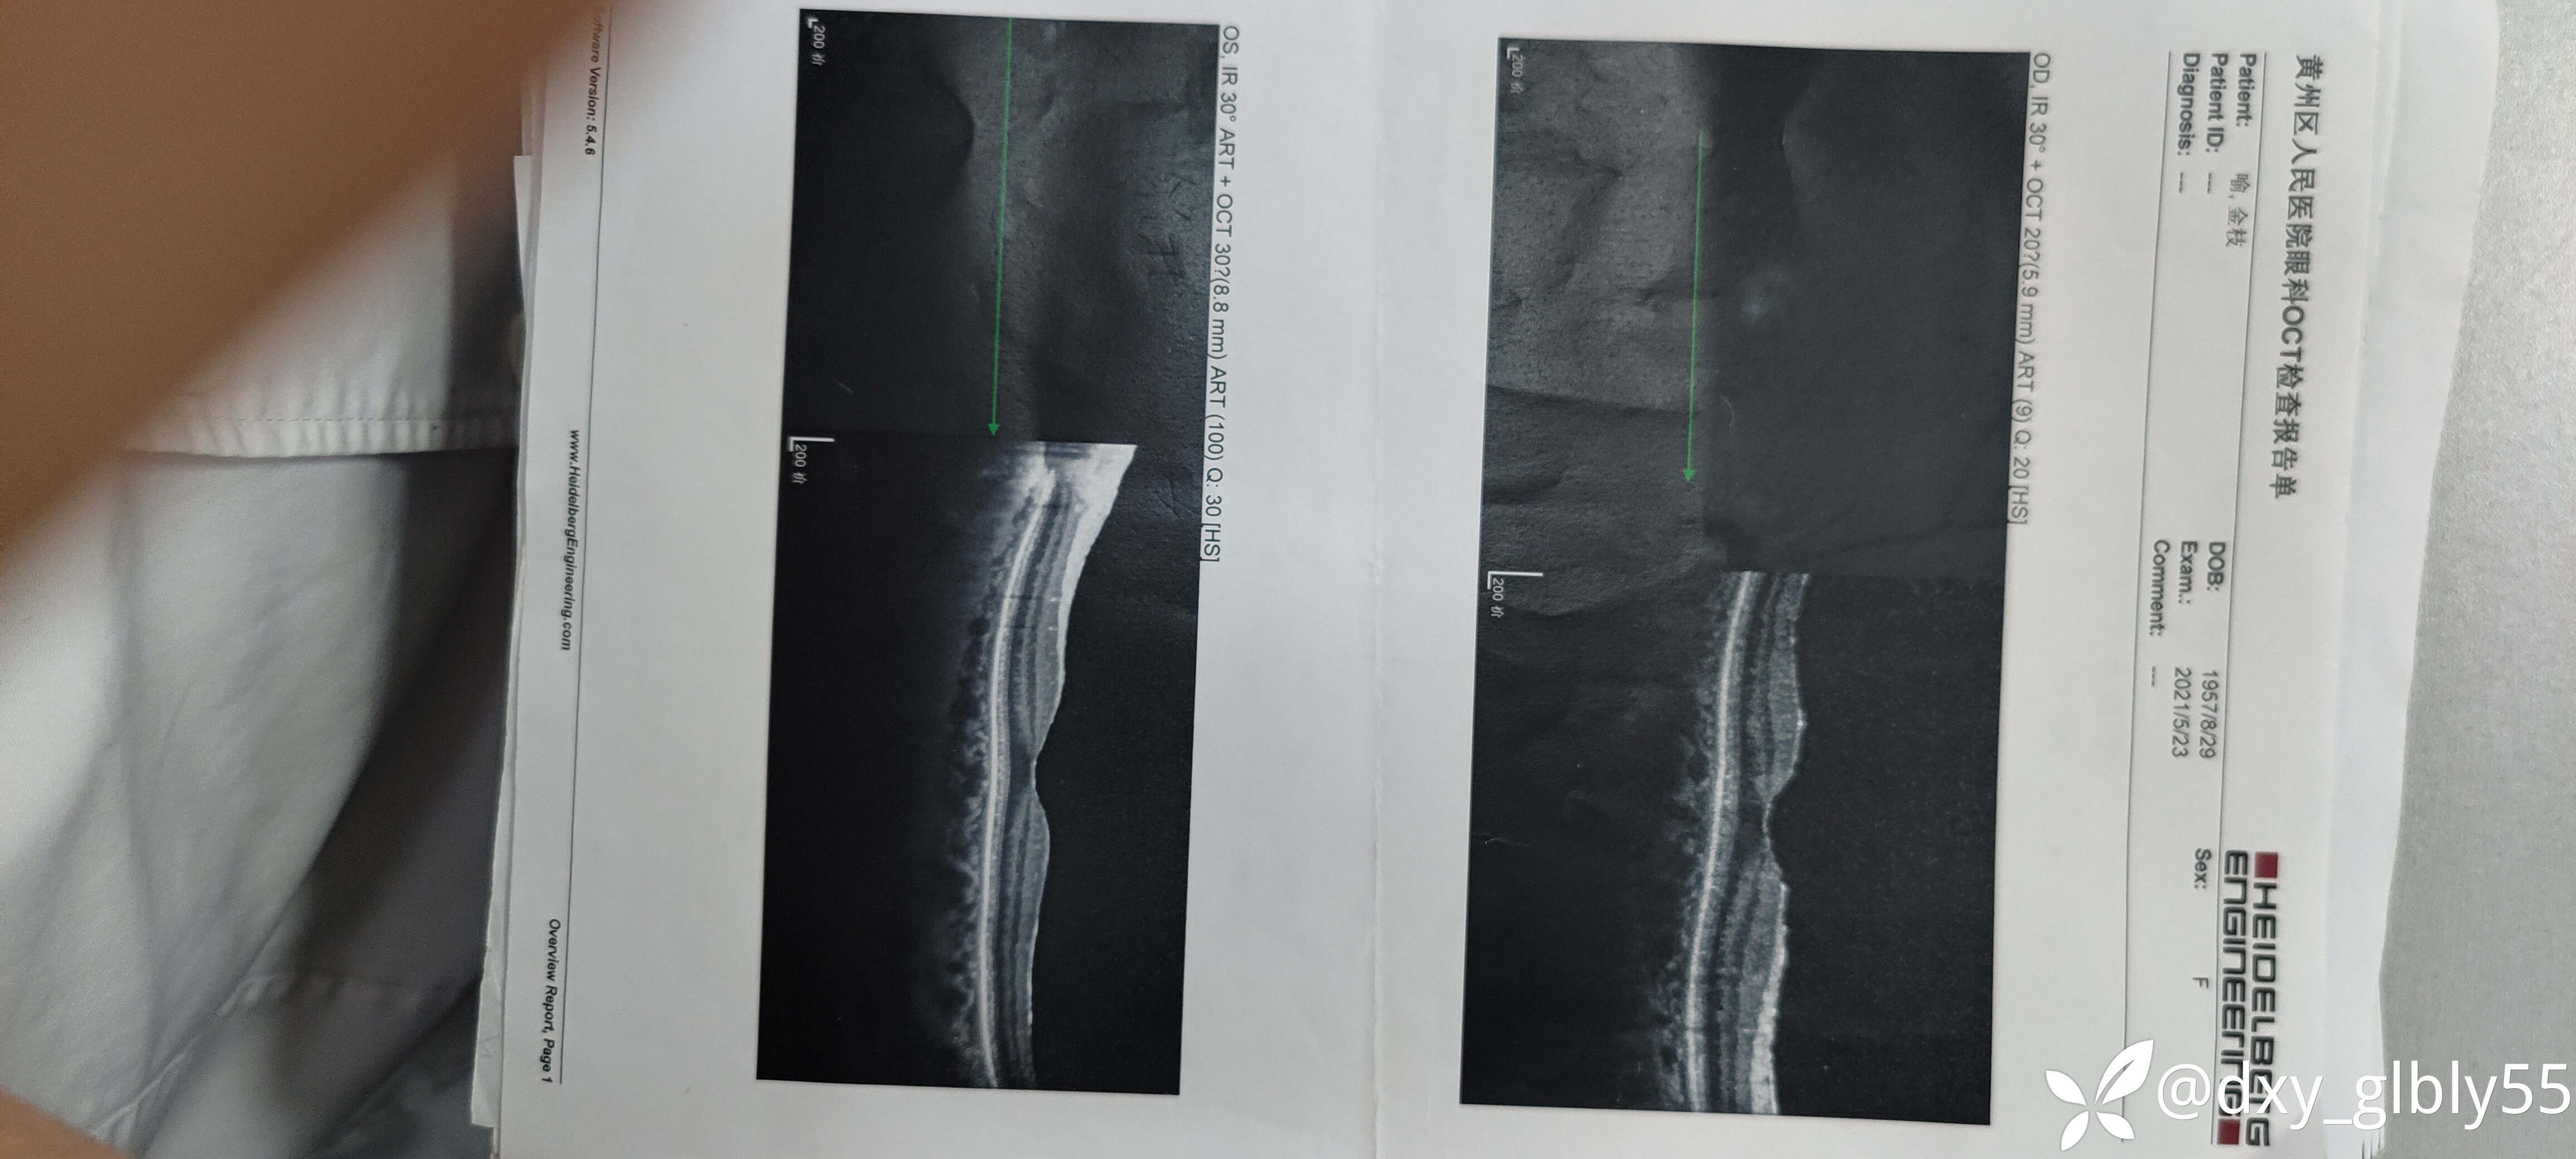

其他的辅助检查显示玻璃体轻度浑浊,未见网脱,出血,炎症反应等表现,oct查黄斑及视盘均未见明显异常。

就诊纪录以及一些有价值的特检结果我放在下面,除了电生理检查有异常在其他的特检没有表现明显的异常

一些特检结果我放在下面,请各位老师帮忙看一下,这个病人看了很多地方,很是苦恼